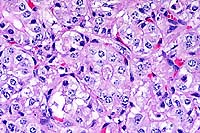

20x

obj

- Case14-2. Liver. Somewhat serpentine arrangements

of arteriolar smooth muscle cells represent portal arteriolar

hyperplasia. Portal veins are not discernable. Scattered hepatocytes

contain brown pigment.